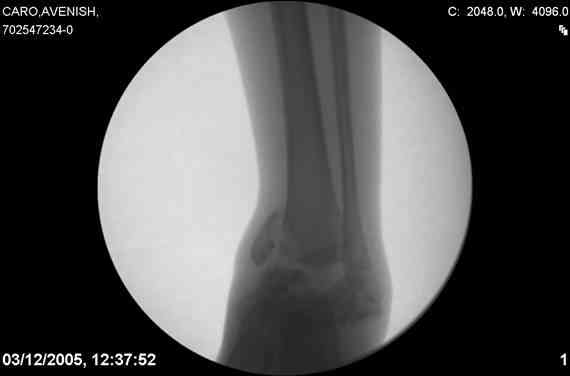

ya by popytalsya sobrat talus anatomichno,seichas pozdno operirovat iz za oteka,po etomy distrakziya apparatom budet optmalna.Posyalu vam podobyai moi sluchai.

14 years old girl

Fall from height ( 3rd floor)

Compressed fractures of L1-L2

Fx of orbital bone

Дорогие Mark Eidelman and A. Liberson. Спасибо за представленные иллюстрации и за дельные советы.

Mark, судя по снимкам в день поступления произведен А.В.Ф., а остеосинтез ч-з какое время произведен?, остеосинтез произвели открытым способом?( на снимке п/о рубцы).

aparat postavlen v den postupleniya,rastaynuli, vpravili zakryto naskolko vozmoghno, a kogda otek spal sdelali otkrytoe vpravlenie.Teryat tut nechego, moghno tolko uluchshit.